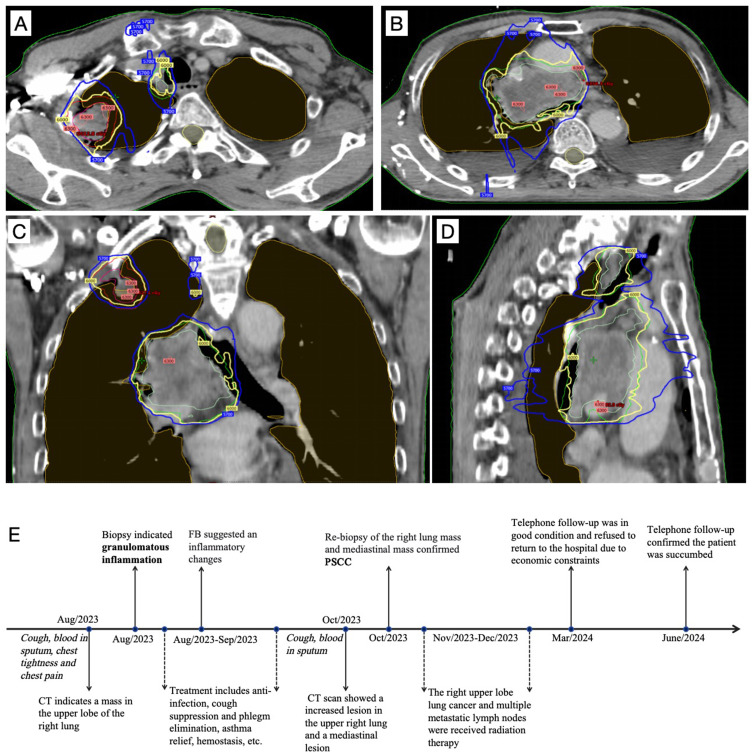

Case presentation: A 66-year-old male visited a local hospital with symptoms such as cough and hemoptysis. A computed tomography (CT) scan of the chest revealed a mass in his right lung, and no mediastinal lymphadenopathy was observed. Bronchoscopy showed no major abnormalities, and the results of fine needle aspiration biopsy showed granulomatous inflammation. Even though the patient received anti-infection treatment, his symptoms did not improve markedly. After two months, a follow-up CT scan of the lung showed a noticeably enlarged mass accompanied by multiple instances of mediastinal lymphadenopathy in the upper lobe of the right lung. Consequently, he underwent a second CT-guided lung biopsy at our hospital. The pathology report indicated PSCC. Due to financial constraints, genetic testing was not performed. Given his poor overall physical condition, the patient was unable to undergo systemic chemotherapy and instead received palliative radiotherapy. The prescribed radiotherapy dose for the right upper lobe lung cancer and multiple metastatic lymph nodes was 60 Gy, administered in 30 fractions. Unfortunately, he failed to adhere to scheduled follow-ups and succumbed to the disease 6 months later, as confirmed during a telephone follow-up.